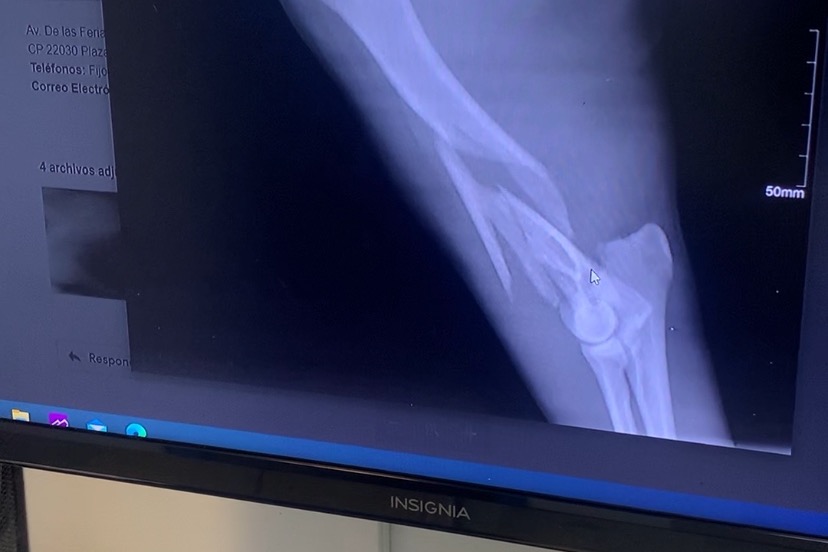

Our dog Max somehow escaped our yard in the early morning of Thursday November 19th and was hit by a car down the street from our house. The car that hit him just took off and left him there. We took him to the vet where we were told he’d need surgery for his front arm and his back leg needed to be stitched up from a huge gash. His front arm is broken in 4 places. Luckily he didn’t die and doesn’t have any internal injuries. He has to stay overnight at the vet until after the surgery and he recovers enough to come home. Max is a super sweet, playful and loving dog and a member of our family. We’re trying our best to deal with this unexpected cost. If anyone could help towards the cost of his surgery we’d be super grateful!